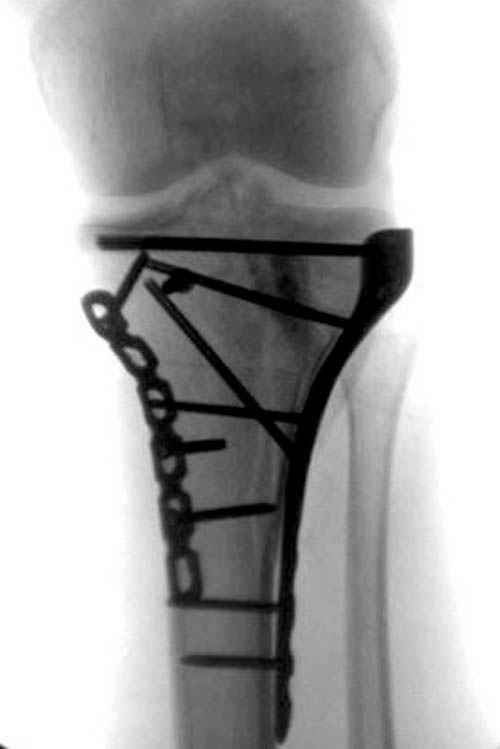

Трудно поверить, что разрекламированная Ортопедическая школа Восточной Украины позволяет такие странные снимки? На прямом снимке сохранен общий контур плато, но не известна судьба импрессии суставной поверхности. На полубоковой?, оставлен без репозиции задне-медиальный отдел, и навряд ли после такой фиксации можно удовлетвориться результатом.

Такая ситуация характерна для многих, когда принимается ошибочное решение, т.е пытаются фиксировать одним имплантом переломы двух мыщелков. Латеральная пластина приемлема только для тех случаев, когда сохраняется интактным медиальный диафизарный кортекс и отсутствует фрагментация на верхушке медиального перелома.

На представленных предоперационных срезах КТ огромный задне-медиальный фрагмент расположен больше кзади, чем медиально. Для планирования, кроме поперечных срезов, надо ориентироваться на корональные срезы, которые укажут топографию верхушки медиального фрагмента.

Представленные снимки не информативны, нужны отдельные качественные снимки коленного сустава и голени без ротации.